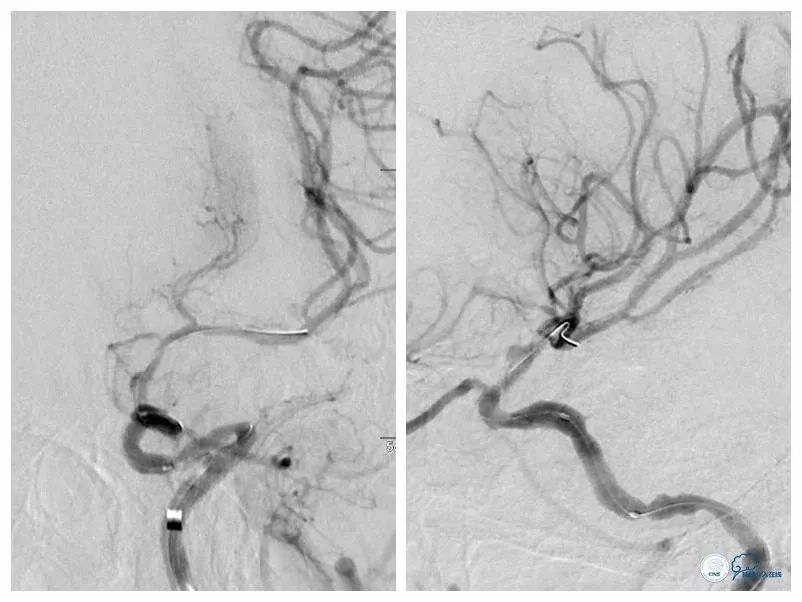

DSA:左颈内动脉C6-7段重度狭窄,狭窄程度重,病变较长,前向血流减慢(图4,5),后循环造影显示后循环向前循环侧支代偿不足(图6)。

图4

图5

图6

全麻下右股动脉入路,8F导引导管至左颈总动脉末端,将6F Navien导管送至左颈内动脉C1段以远,造影示左颈内动脉C6-7段长段狭窄,狭窄率约90%,长度约10mm(图7)。

图7